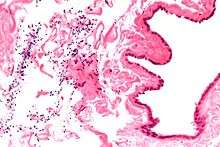

Spermatocele (/spɜːrˈmætəsiːl/[1][2]) is a retention cyst of a tubule of the rete testis or the head of the epididymis distended with barely watery fluid that contains spermatozoa. Spermatoceles are the most common cystic condition encountered within the scrotum. They vary in size from several millimeters to many centimeters. Spermatoceles are generally not painful. However, some men may experience discomfort from larger spermatoceles. They are harmless.